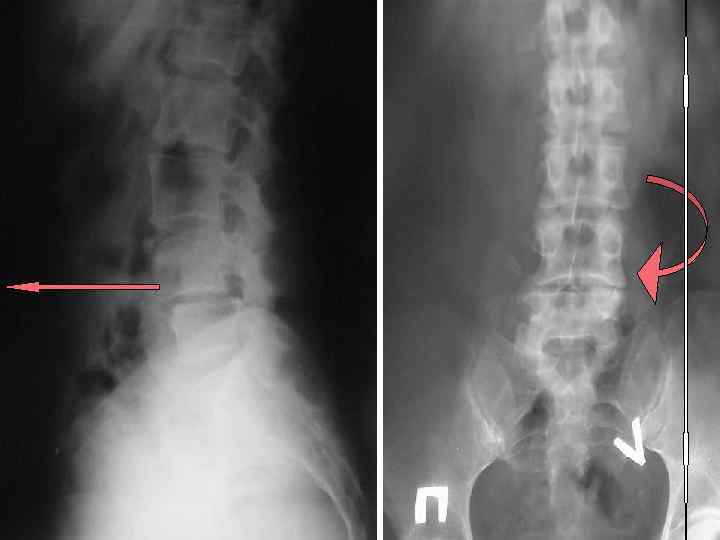

Спондилолиз Спондилолистез

Спондилолистез